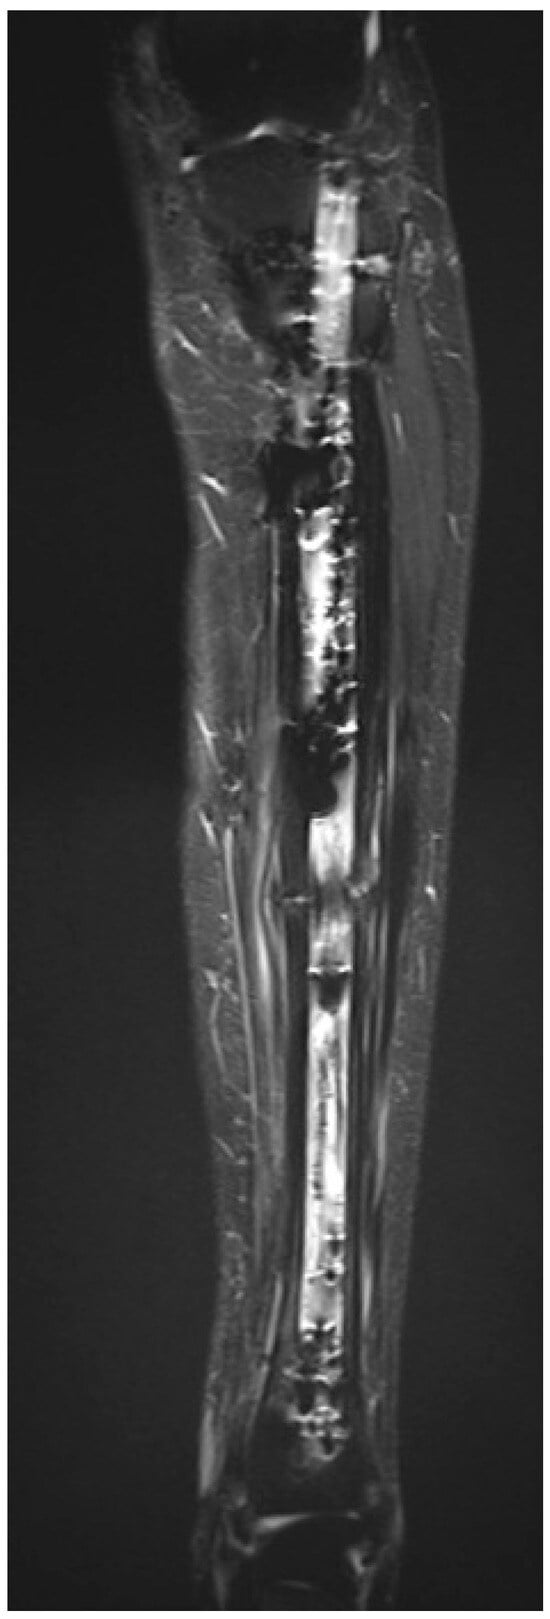

Figure 6.

Sequential anteroposterior radiographs following retrograde tibial bone transport at direct postoperative, 5 weeks, 4 months, 8 months, and 1.5 years. The initial segmental defect measured 9 cm. Remaining defect measured 8.5 cm at 5 weeks, 7 cm at 4 months, 1.5 cm at 8 months, and fully consolidated at 1.5 years. Progressive transport and callus formation are evident, with complete restoration of tibial length and alignment at 1.5 years. Distances are approximate due to image scaling.